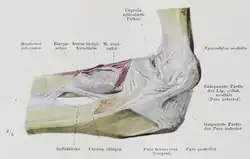

Deskriptive Anatomie

_-_Fig._304.png)

Der Biceps brachii entspringt am Schulterblatt und endet am Ellenbogen; folglich verläuft er über den Oberarmknochen hinweg ohne, dass er an diesem inseriert (zweigelenkiger Muskel)[2].

Der Biceps liegt mit der Hauptmasse seines Muskelbauches an der Vorderseite des Oberarms und bildet dort im kontrahierten Zustand einen kräftigen und deutlich vorspringenden rundlichen Wulst, welcher das Oberflächenrelief des Arms deutlich bestimmt.

Der Biceps besteht aus zwei Köpfen, die beide ihren Ursprung vom Schulterblatt nehmen. Weil der Musculus deltoideus in diesem Bereich jedoch über den beiden Köpfen liegt, ist die Teilung von außen nicht zu sehen. Die beiden Muskelköpfe vereinigen sich etwa dort, wo sie sichtbar werden, zu einem einzigen Muskelbauch.

Ursprung

Der lange Kopf, Caput longum, entspringt oberhalb der Cavitas glenoidalis von dem Tuberculum supraglenoidale sowie vom Labrum glenoidale. Er besitzt eine lange, dünne, gekrümmte Ursprungssehne, die zunächst frei durch das Schultergelenk, dann durch den Sulcus intertubercularis, umgeben von einer dünnen Aussackung der Gelenkkapsel, der Vagina synovialis intertubercularis, nach abwärts zieht, um in Höhe des Deltoideusansatzes in den Muskelbauch überzugehen. Die Ursprungssehne verbreitert sich konisch an der Stelle, wo sie den Sulcus intertubercularis verlässt; hierdurch wird vermieden, dass sich Muskelfasern hier abscheuern können.[3]

Der kurze Kopf, Caput breve, entspringt gemeinsam mit dem Coracobrachialis und mit dem Pectoralis minor von der Spitze des Processus coracoideus.

Ansatz

Der Muskelbauch geht dicht oberhalb des Ellenbogengelenks in eine kräftige Endsehne über und setzt circa 4 cm unterhalb des Gelenkspaltes an einem kräftigen Muskelhöcker (Tuberositas radii) der Speiche (Radius) an. Hier findet man einen Schleimbeutel, die Bursa bicipitoradialis, welcher die Endsehne umgibt. Zwischen der Sehne und der Ulna ist noch ein weiterer, kleiner Schleimbeutel, die Bursa cubitalis interossea, eingeschaltet.

Zudem zweigt sich noch eine oberflächliche Sehne ab, die als Aponeurosis musculi bicipitis bzw. als Lacertus fibrosus (lat. sehniger Muskelursprung) bezeichnet wird und in die Unterarmfaszie (Fascia antebrachii) ausstrahlt. Man kann diesen am besten tasten, wenn man den Unterarm in etwa 60° Flexion- und Supinationsstellung führt und dann vom Sulcus bicipitalis medialis aus nach distal tastet[1].